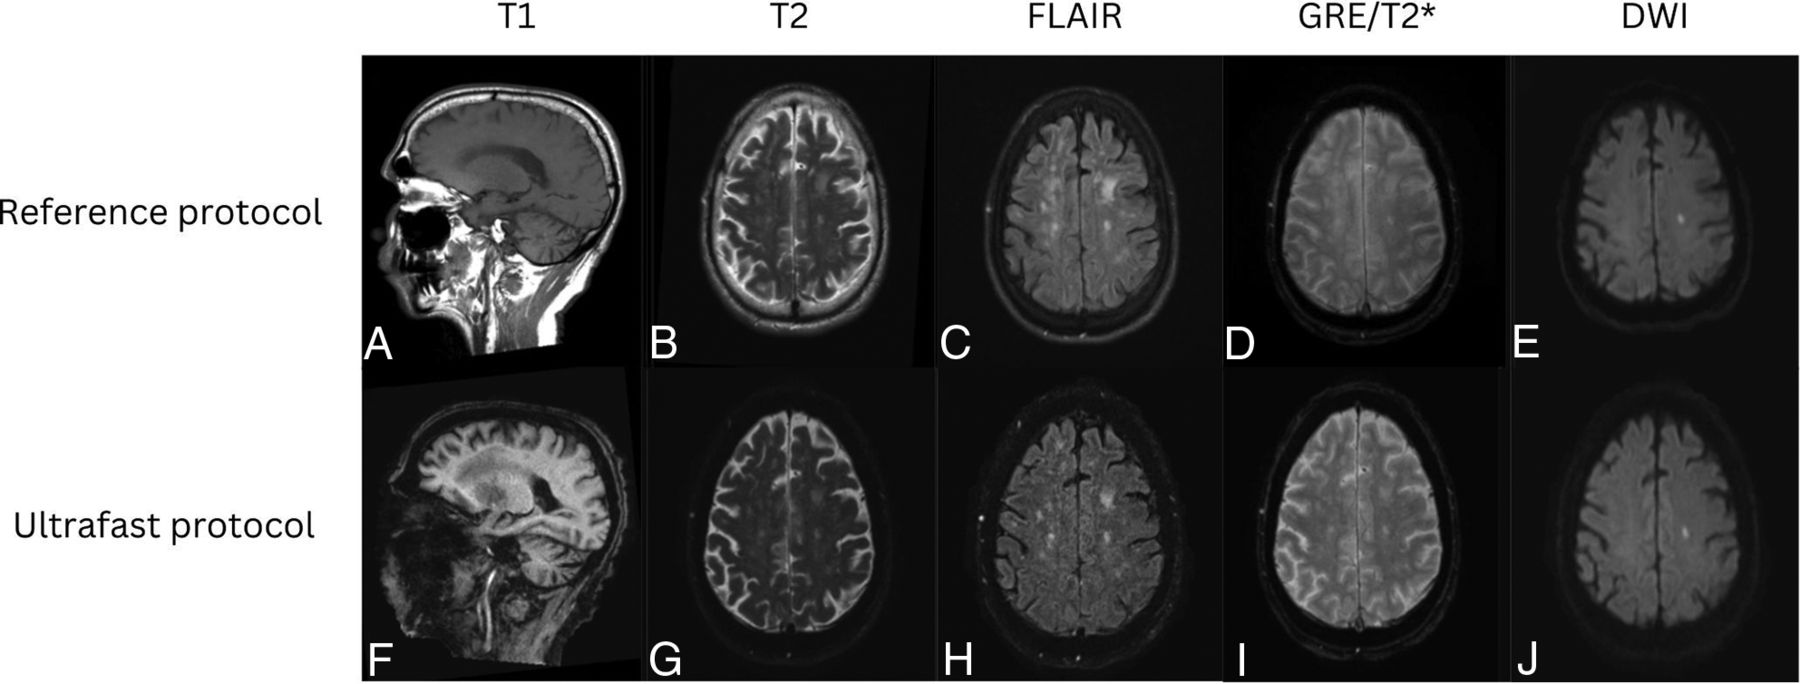

Representative images from 4 clinical cases are shown in Figures 3⇓⇓–6, demonstrating similar diagnostic quality between the ultrafast brain MR protocol images and the reference brain MR protocol images. Figure 3 shows a case of amyloid angiopathy with scattered foci of microhemorrhages. There is blurring of the findings on the reference GRE sequence due to motion artifact, and the foci of susceptibility signal are better appreciated on the ultrafast T2* images. Figure 4 shows a case of herpes simplex virus encephalitis with T2/FLAIR hyperintensity and restricted diffusion in the left greater than right mesial temporal lobes, visualized equally well on both the reference and the ultrafast brain MR protocols. Figure 5 shows a case of punctate subacute infarct in the left centrum semiovale on a background of chronic small vessel ischemic disease, visualized equally well on both the reference and the ultrafast brain MR protocols. Figure 6 shows a case of glioma involving the left thalamus with both the reference and the ultrafast brain MR protocol demonstrating ill-defined T2/FLAIR hyperintensity centered in the left thalamus.

Patient with a low-grade left thalamic glioma. Reference sagittal T1-weighted (A), and axial T2-weighted (B), FLAIR (C), SWI (D), and DWI (E) show an ill-defined, mildly expansile, T1 hypointense, and T2/FLAIR hyperintense lesion centered in the left thalamus, compatible with diagnosis of low-grade glioma. Similar findings were appreciated on the ultrafast sagittal T1-weighted (F), axial T2-weighted (G), FLAIR (H), SWI (I), and DWI (J).